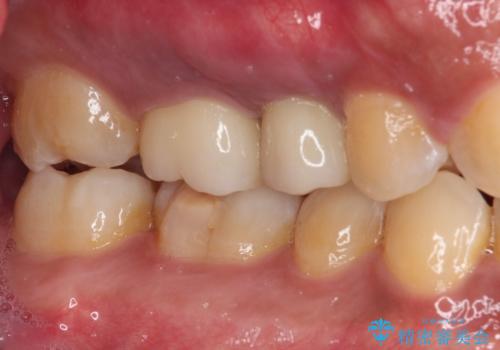

破折して抜歯が必要となった歯の後ろの歯は、根管治療が必要な状態であったので、根管治療を行い、矯正治療後にインプラント部の補綴治療と同時にセラミッククラウンを装着しました。

矯正治療以外に費用負担がかかることになりましたが、気になるところ全てを処置することができ、患者様には大変満足していただきました。